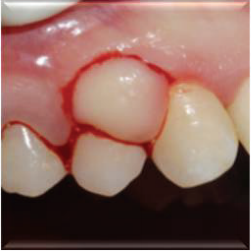

口内检查发现患者13、14牙间牙龈肿胀,质硬,无蒂,牙龈周围轻度菌斑堆积,牙龈轻度红肿。13、14牙不松动。

计划切除增生牙龈。由于增生范围较大,拟利用腭侧牙龈进行软组织修复。